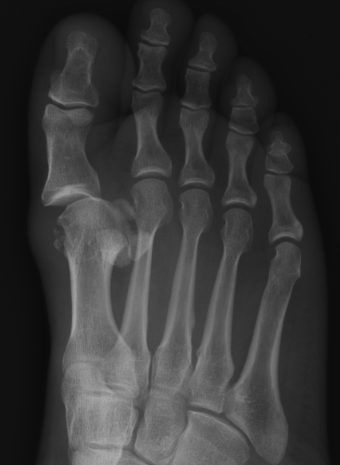

Great toe MTPJ dislocation

Pathology

Hyperdorsiflexion

Metatarsal head dislocates plantar

- tear of plantar plate / disruption bipartite sesamoid

- may buttonhole through capsule / plantar plate

Xray